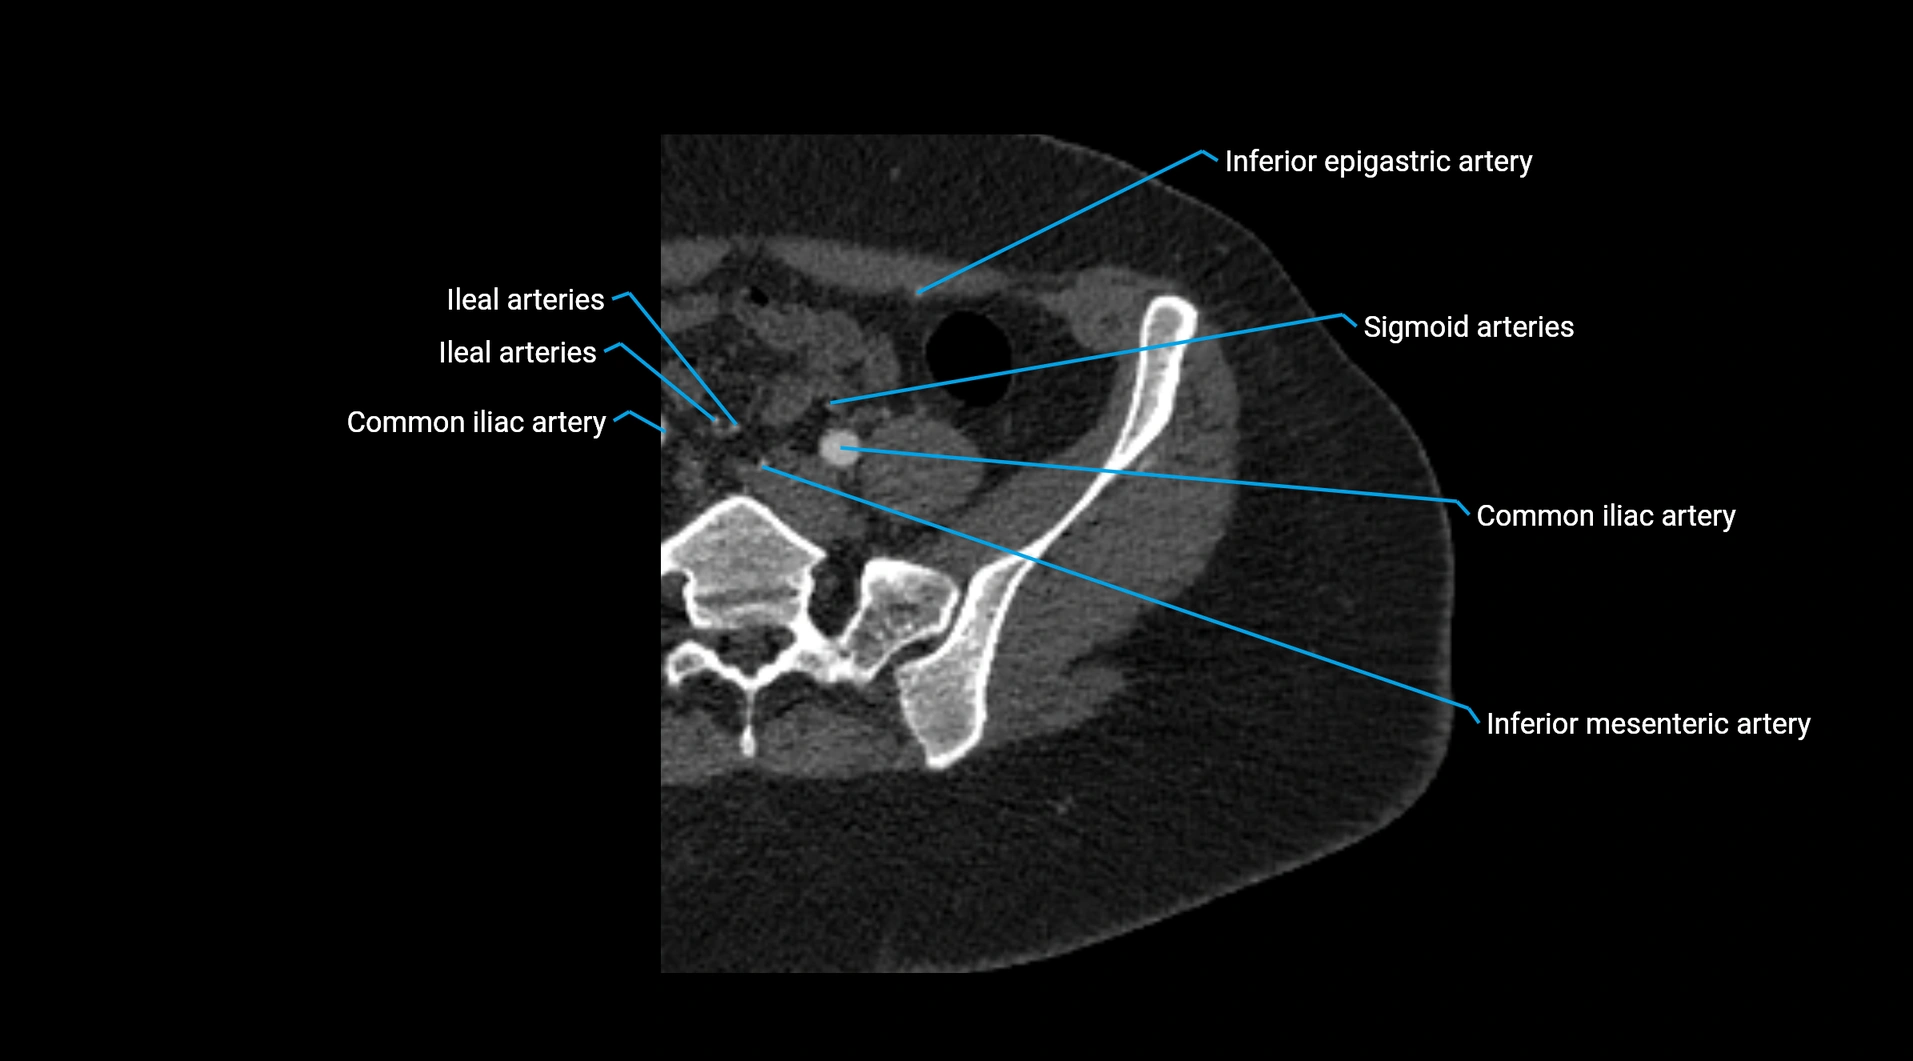

CT images

image